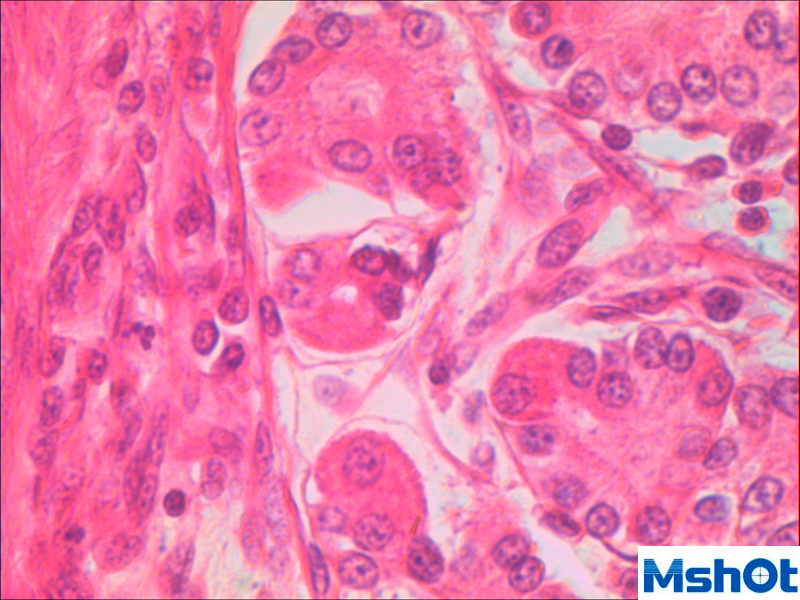

生產(chǎn)質(zhì)量管理規(guī)范規(guī)定:產(chǎn)品在包裝前,企業(yè)質(zhì)量檢驗部門應(yīng)對每批產(chǎn)品,按國家標(biāo)準(zhǔn)或經(jīng)審核批準(zhǔn)的產(chǎn)品標(biāo)準(zhǔn)進行檢驗。知名品牌公司廣西兩面針公司始終按生產(chǎn)質(zhì)量管理規(guī)范規(guī)定生產(chǎn)經(jīng)營,兩次榮獲全國五一勞動獎狀,公司領(lǐng)導(dǎo)人兩次榮獲全國五一勞動獎?wù)拢啻潍@得全國輕工系統(tǒng)、廣西壯族自治區(qū)勞動模范稱號。近段時間,廣西兩面針公司擴大生產(chǎn)規(guī)模,為了生產(chǎn)出讓人民放心的產(chǎn)品,準(zhǔn)備采購獲得進口熒光顯微鏡|顯微鏡攝像頭|顯微鏡接口對產(chǎn)品進行檢測.我司銷售工程師給他們推薦了熒光顯微鏡|顯微鏡攝像頭|顯微鏡接口ME21.經(jīng)過廣西兩面針公司的技術(shù)工程師對國內(nèi)幾家比較有名的熒光顯微鏡|顯微鏡攝像頭|顯微鏡接口產(chǎn)品測試對比,覺得明美公司的熒光顯微鏡|顯微鏡攝像頭|顯微鏡接口ME21的參數(shù)都比較符合他們的需求。最終選擇了技術(shù)實力雄厚和售后服務(wù)到位的廣州明美公司的熒光顯微鏡|顯微鏡攝像頭|顯微鏡接口ME21下面是這套產(chǎn)品所拍的圖片效果:

明美提供的儀器